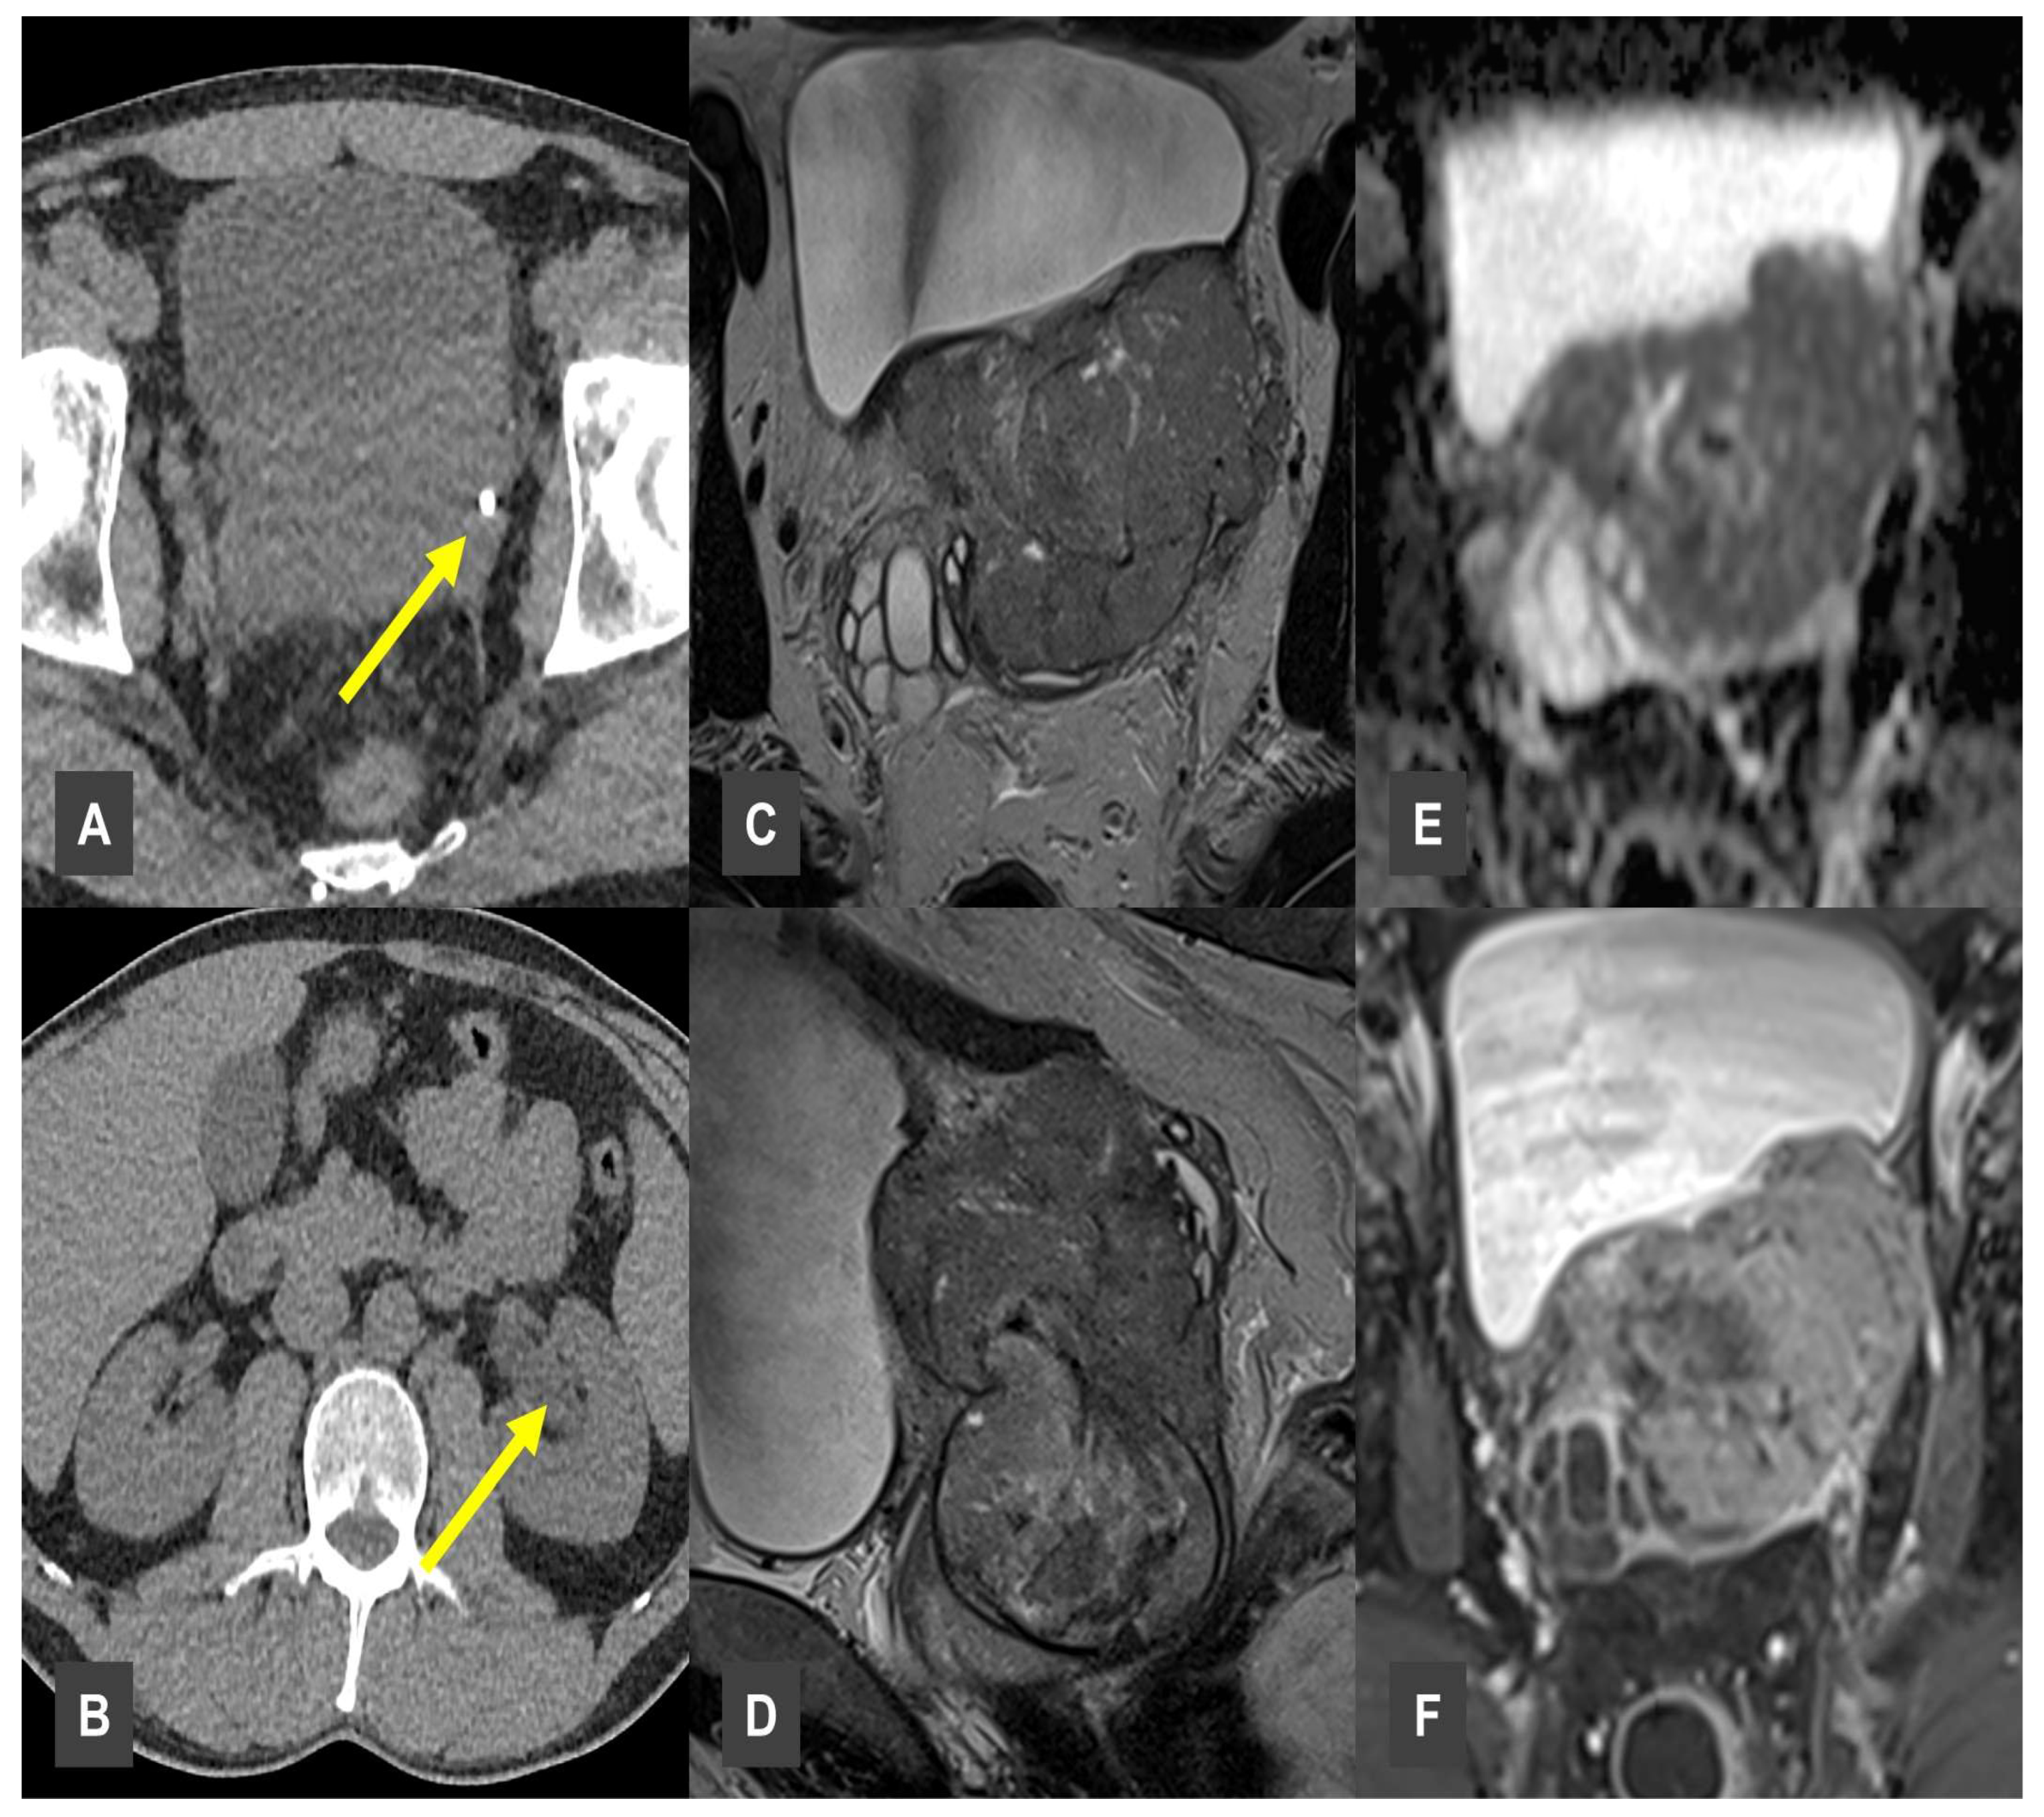

A particularly case in our study involved a 43-year-old patient who was referred to our clinic due to unexplained flank pain. Initial sonography revealed an unclear intrapelvic mass. A subsequent CT scan confirmed the presence of the intrapelvic mass, as well as a radiopaque structure in the left perivesical region, initially interpreted as a urinary calculus (Figure 5A). Additionally, ipsilateral hydronephrosis was observed (Figure 5B). The lesion was initially diagnosed as prostatitis, based on clinical findings and patient age; however, further workup was recommended to exclude prostate cancer. For further diagnostic evaluation, MRI was performed, which supported the suspicion of a malignant lesion. The MRI revealed a T2-weighted hyperintense, infiltrative pelvic mass, involving the left ureteral orifice (Figure 5C,D). The lesion demonstrated restricted diffusion and marked contrast enhancement (Figure 5E,F). Malignancy was confirmed histologically via biopsy, diagnosing an infiltrating sarcoma.

Figure 5. Prostate infiltrating Sarcoma. (A,B) CT showing urolithiasis with obstructive changes (yellow arrows). (C,D) MRI demonstrating a large T2w hypointense pelvic mass. (E) Diffusion-weighted MRI showing diffusion restriction within the pelvic lesion, suggestive of high cellularity. (F) Lesion expressed vivid contrast enhancement.